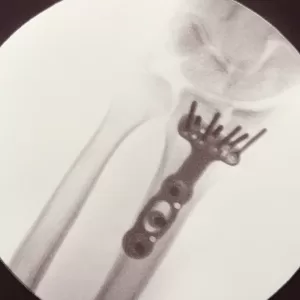

A few years ago, I experienced a broken wrist in a high-speed cycling crash. I had surgery on the wrist and went through occupational therapy, and eventually returned to playing the guitar. I hadn’t thought to share my experience with other guitarists because I assumed that every break is unique, but this winter my wife had a Colles’ fracture of her wrist in a fall while hiking. Her ER x-ray looked very similar to mine and her post-surgical x-ray was also almost identical, which made me think that maybe my experience wasn’t so unusual after all. So, in hopes that this helps someone else who is rehabbing from a Colles’ fracture and hopes to start or continue playing guitar, I’ll tell you a bit about my experience. I should mention that I broke my left wrist — the wrist on the fretting side, not the strumming side.

A Colles fracture is a fracture of the distal radius, which is fancy medical talk for “breaking off the end of the big bone in your forearm”. There are two bones in your forearm, and the radius is the one closer to your thumb. A Colles fracture is so-named because this sort of fracture is so common (it is a common result of falling down on an outstretched hand) that a surgeon named Abraham Colles wrote a study of them in the mid- 19th century.

The other thing that is almost unique about playing the guitar is the need to be able to press down with your fingers/fingertips without actually closing your fist. There weren’t any exercises in my PT regimen that demanded that particular skill. I found that trying to fret the guitar, even when my wrist permitted me to get into position, was fairly painful, and took a while to come back. Perhaps this had to do with inflammation in my wrist after surgery, as the tendons that are needed to close my hand run right across the metal plate that supports my wrist.